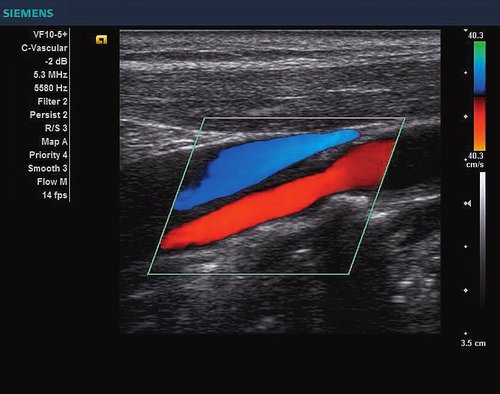

Siemens ACUSON X300 PE Beschreibung

• Powermode

• Features: 3D, 4D, Farb/Doppler